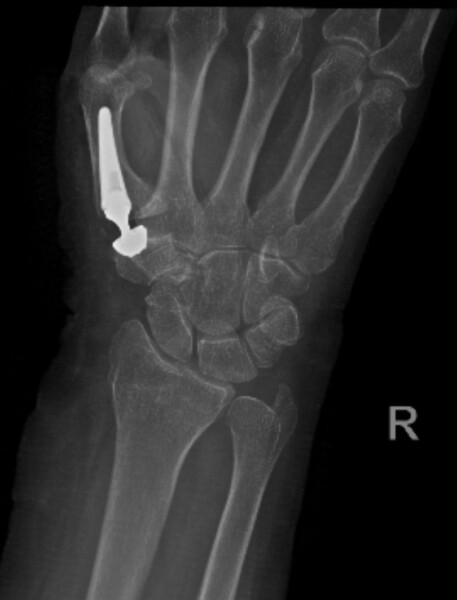

El médico, quien además es miembro Titular de la Asociación Argentina de Cirugía de Mano y Reconstructiva de Miembro Superior, explicó que la paciente se trataba de una mujer de 73 años, con una vida muy activa, que padecía de artrosis en la base del pulgar derecho, muy avanzada y con incapacidad funcional. Por ese motivo se decidió realizar una artroplastia con una prótesis total de la articulación carpo metacarpiana del pulgar ya que la misma le facilita una recuperación fácil, rápida y principalmente pasando el dolor en poco tiempo.

Dr. Juarez Cesca: La cirugía básicamente consiste en reemplazar la articulación de la base del pulgar, que es la articulación carpo metacarpiana del pulgar, por una articulación nueva, que sería la prótesis. Para ello, sacamos parte de los huesos y reemplazamos con la prótesis. La prótesis es exactamente lo mismo, como para que se pueda describir, es como una prótesis de cadera pero en el pulgar, hasta la forma es prácticamente la misma, nada más que otro tamaño y va en la base del pulgar.

Dr. Juarez Cesca: El material que tiene la prótesis es titanio y tiene un componente de hidroxiapatita que lo fija al hueso, es titano e hidroxiapatita, no lleva cemento para adherirse a la superficie. Todo esto de la hidroxiapatita hace que se vuelva rugosa la estructura, se fije y se asocie al hueso.

Dr. Juarez Cesca: Hay que dejar en claro que una prótesis está orientada a suplantar una articulación que no funciona por X motivos y la ventaja de toda prótesis y más que nada para esta patología que es la rizartrosis o artrosis de la base del pulgar logra la movilización temprana. Existen otras cirugías para las artrosis de la base del pulgar pero la recuperación es mucho más larga y dolorosa, sin prótesis. Con la prótesis el paciente al mes ya está usando su mano, en cambio con otro tipo de prácticas con interposición, se les dice, necesita aproximadamente entre 4 y 6 meses de recuperación.